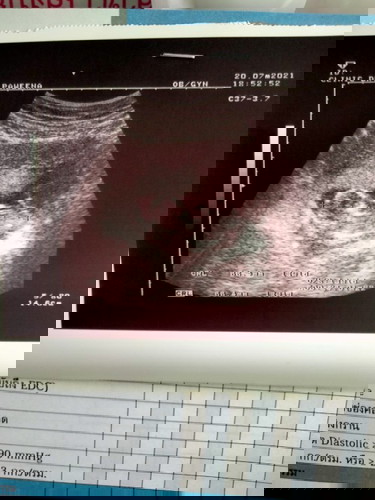

หนูน้อย14+5ท้องสองค่ะ

แม่เริ่มท้องออกแล้วทีมมกราคมค่ะหมอบอกผู้ชายยยแต่รอลุ้นอีกทีเดือนหน้าจ้า